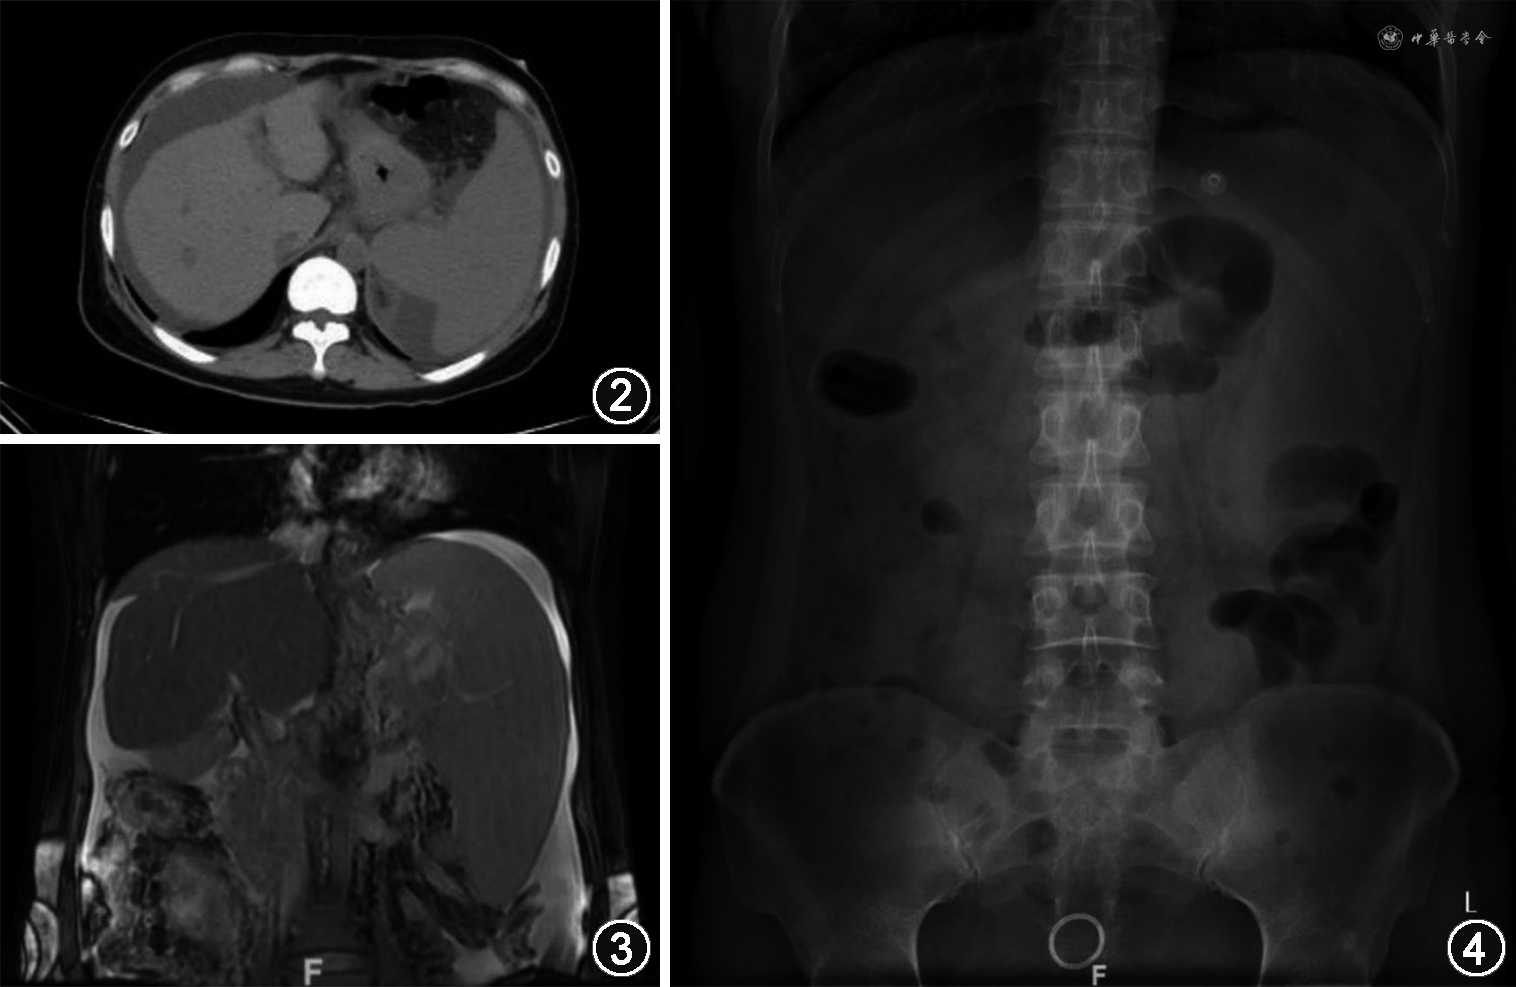

患者女,39岁,以腹胀5年余,黑便1个月余,呕血6 d,腹痛3 d于2015年2月17日收入北京协和医院消化科。2010年因腹胀在当地医院行超声:门静脉血栓形成、肝弥漫性病变、脾大和腹水。腹部增强CT:肠系膜上静脉主干血栓形成;食管胃底静脉曲张,多发侧支循环开放;肝弥漫性病变,肝内胆管扩张,胆管壁弥漫性增厚;脾大伴脾梗死;腹水。胃镜检查:食管静脉曲张(程度不详)。予利尿等处理后腹胀减轻。3个月前患者食用燕麦后出现成形黑便,1~2次/d,50~150 ml/次,外院查粪便OB(+)。6 d前呕鲜血,总量500~1000 ml。我院急诊查血常规:白细胞(WBC)12.65×109/L,血红蛋白(Hb)68 g/L,血小板(PLT)397×1012/L;凝血酶原时间(PT)>70 s,国际标准化比值(INR)>6.0,活化部分凝血活酶时间(APTT)120.6 s。予禁食,补液,静脉泵入奥美拉唑及生长抑素,输注红细胞、血浆、凝血酶原复合物后呕血停止。胃镜示:重度食管静脉曲张(图1)。3 d前出现腹胀、腹痛,停止排气排便,予灌肠治疗后好转。腹腔血管超声:腹腔干及肝动脉内径增宽,血流速度增快,门静脉未见血流信号;肠系膜上动脉未见明显异常;肠系膜上静脉、肠系膜下动静脉显示不满意。以“门静脉高压、消化道出血”收入院。

2016年4月5日行食管静脉曲张套扎治疗。术后恢复顺利,停用华法林。监测PLT逐渐升至510×109/L,开始羟基脲治疗,未再发生消化道出血。2020年12月1日消化科随诊,血WBC 8.40×109/L,Hb 140 g/L,PLT 393×109/L;ALT 27 U/L,Alb 39 g/L;PT 16.0 s,INR 1.42,APTT 33.9 s;门静脉及腹部超声基本同前。次日行胃镜:食管静脉曲张套扎治疗后,未见新曲张静脉;贲门处可见新生血管,再次予硬化剂和组织胶局部注射(图5)。